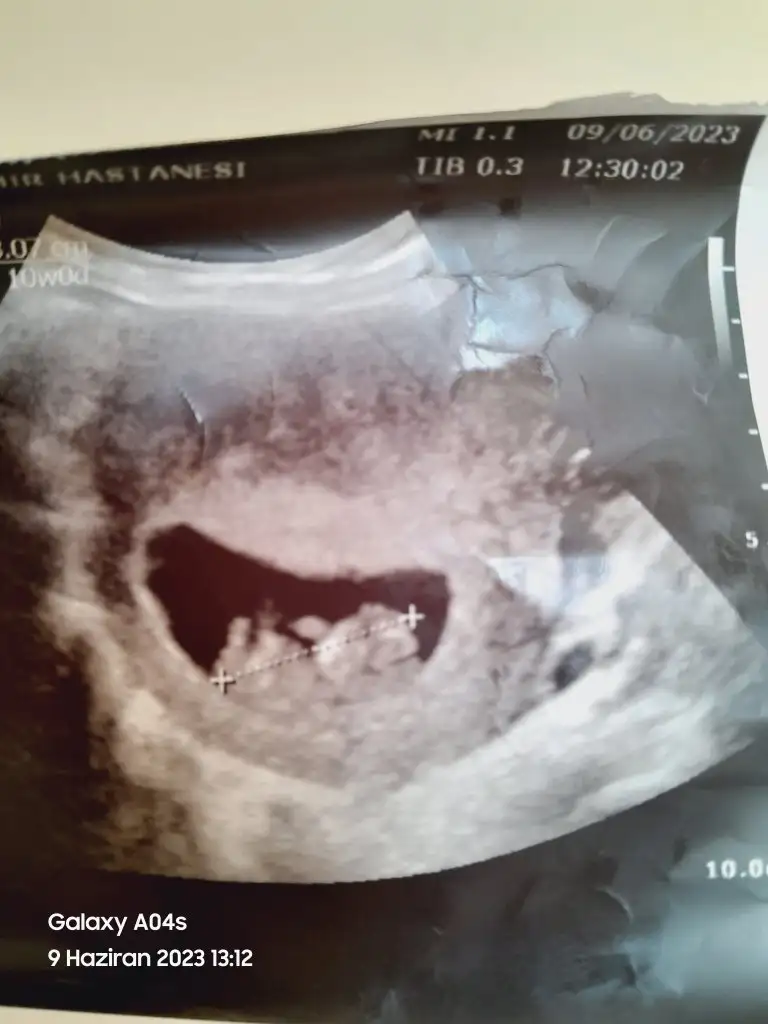

Birkac gun oynayabiliyorAhahah ne anladınızyurtdisindayim yarın ülkeye dönüyorum ve hemen yarına randevu aldım inşallah ilk kez bakacağım durum nedir diye:) 8 hafta mi oluyor? Ben 7 sanıyordum ya :)))